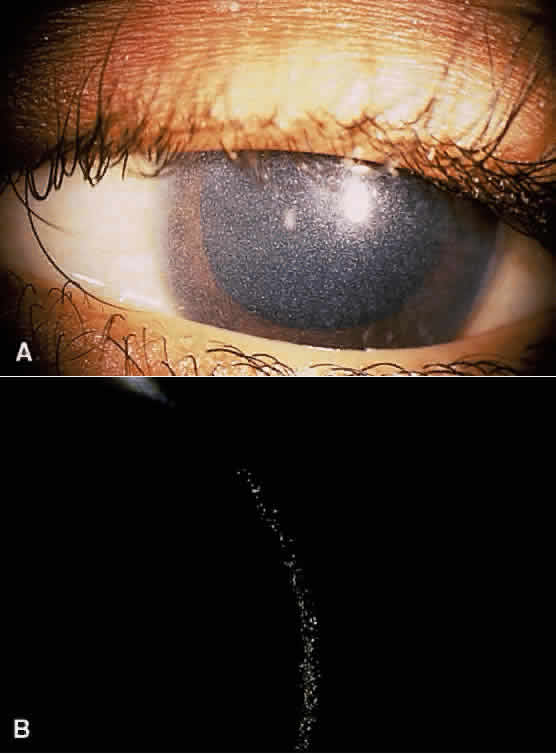

Albinism comprises a heterogeneous group of clinical syndromes exhibiting hypomelanosis based on heritable metabolic defects of the melanin pigment system. All types of albinism are characterized by foveal hypoplasia, nystagmus, photophobia, and decreased visual acuity in addition to absent or decreased melanotic pigment in skin, hair, and eyes (oculocutaneous albinism [OCA]) or in the eye alone (ocular albinism).31 The term albinoidism refers to hypomelanotic disorders in which the patients do not have nystagmus, decreased visual acuity, or foveal hypoplasia. Eleven disorders have been identified with clinical features of oculocutaneous albinism and four with features of ocular albinism (Table 4). The ocular findings in oculocutaneous albinism are listed in Table 5 (Figs. 2 and 3).

Children with nephropathic cystinosis usually develop severe photophobia within the first few years of life. Slit-lamp examination discloses diffuse scintillating, tinsel-like crystals of the cornea, conjunctiva, and iris (Fig. 6).74–76 Initially, the iridescent crystals occupy the full stromal thickness only in the periphery, while centrally the anterior half to two thirds of the stroma is involved. In patients with longstanding disease, thinning and focal breaks in Bowman's membrane may be present and contribute to the development of severe photophobia.77 Corneal sensitivity may be reduced.78